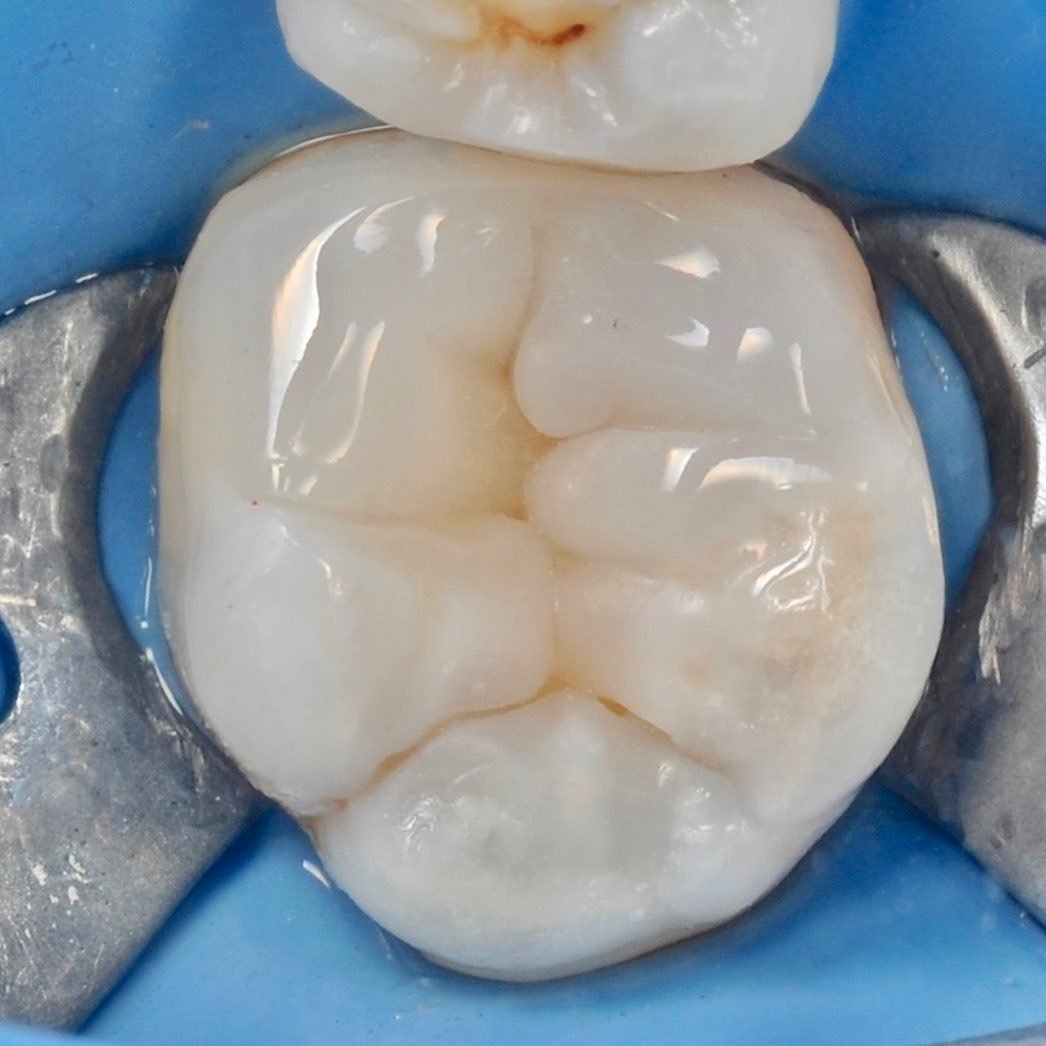

The use of a microscope in dentistry is an ultra-modern direction. Optical instruments allow for constant monitoring of the treatment process, which directly affects the quality of treatment and is aimed at preserving tooth tissues.

The microscope illuminates and enlarges the working field by about 25 times, which helps to accurately determine the anatomical structure of the tooth and restore it with maximum accuracy.

Successful endodontic treatment requires careful preparation, disinfection and sealing of the canals.

Dental treatment under a microscope

Multiple increase

careful treatment of canals